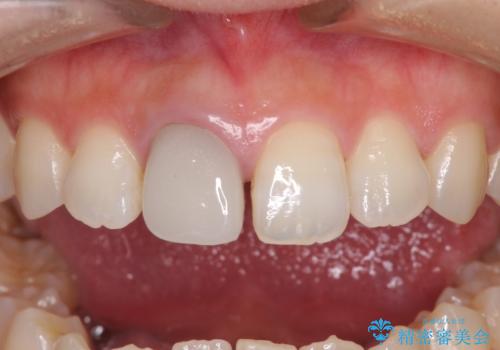

- 近医にて被せた前歯のクラウンの色の違いを気にして来院された患者様です。

オーダーメイドのオールセラミッククラウンにて補綴することとしました。

元々すきっ歯であったため、隙間を全て埋めると左右で大きさがアンバランスとなることが懸念されました。

違和感のない程度に隙間を小さくして、自然な見た目に仕上げました。